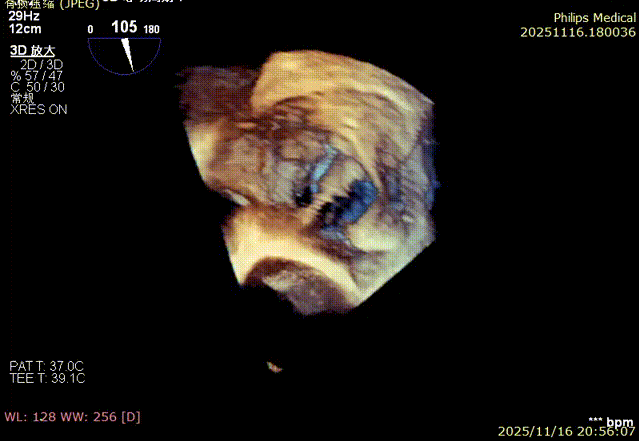

Echocardiographic Assessment: Echocardiography revealed left atrial enlargement. The left atrial appendage (LAA) orifice was 32mm with no thrombus inside. Tricuspid regurgitation was extreme (average vena contracta 18mm). Regurgitant jets were located at the anterior-septal, central, and posterior-septal commissures, with a central gap measuring approximately 13x5.9mm. The annulus was mildly dilated (average diameter 43mm). The tricuspid leaflets showed thickening and degenerative changes.

Systolic Tricuspid Annulus: Circumference 138mm, Area 1468mm².

Diastolic Tricuspid Annulus: Circumference 145mm, Area 1646mm².

Annular area reduction: 50%

preoperative

postoperative

- Annulus Area Reduction: Decreased by 50%.